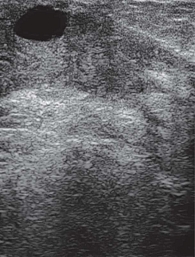

Рис. 5. Эхограмма гигантской ювенильной фиброаденомы левой молочной железы у 13-летней девочки

На УЗ-картине солидное, гипоэхогенное по сравнению с тканью МЖ образование однородной структуры, с четкими контурами. Нередко наблюдается дорсальное псевдоусиление без акустической тени (рис. 3–5) [5, 7, 10].